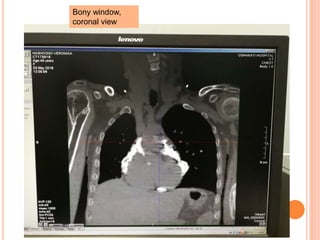

Bony Window,

Sagittal view

coronal view